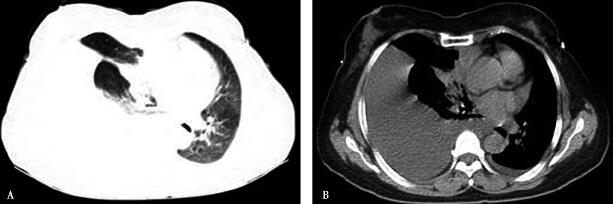

患者反复胸腔穿刺排液,症状略好转。同时实验室检查结果:①两次行胸膜腔穿刺术,分别抽出胸腔积液240ml,胸腔积液常规提示外观均为血性,蛋白均阳性,总细胞数分别为41816/mm3、36500/mm3,有核细胞数分别为2024/mm3、1500/mm3,中性粒细胞百分比分别为10%、9%,淋巴细胞百分比分别为60%、62%,间皮细胞百分比分别为30%、29%,比重均为1.035;胸腔积液腺苷脱氨酶(ADA)分别为16.2IU/L、14.6IU/L(0~25IU/L),乳酸脱氢酶(LDH)分别为703IU/L、582IU/L,蛋白分别为50.7g/L、48.9g/L;胸腔积液癌胚抗原(CEA)分别为3.73ng/ml、3.54ng/ml; 于2012年9月13日行胸腔穿刺置管引流术,先后两次抽出血性胸腔积液240ml、1000ml四次胸腔积液脱落细胞学均见淋巴细胞及间皮细胞,未找到肿瘤细胞。②胸部CT(图1,A肺窗、B纵隔窗):右侧胸腔积液伴右下肺膨胀不良,右肺中叶不张,前下纵隔多发肿大淋巴结,腹腔积液。因仍未能明确诊断,2012年9月18日行胸膜活检术,送检病理未找到肿瘤细胞。

图1